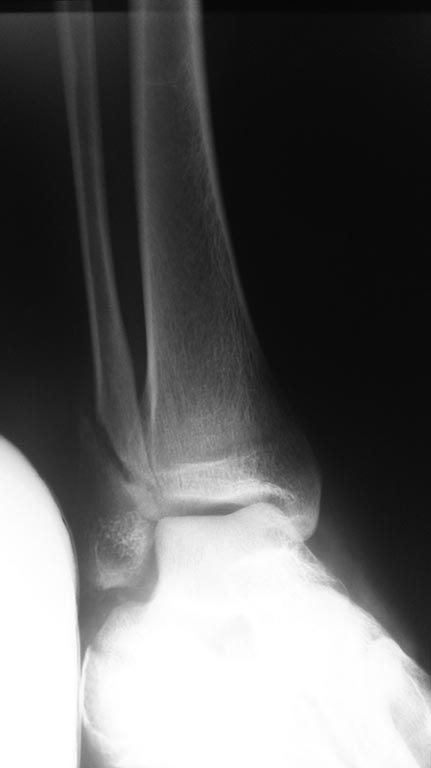

Р

2

3